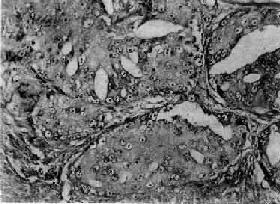

图14-5 前列腺癌(低分化型) 癌细胞异型明显,并呈筛状结构 【转移及扩展】 前列腺癌的蔓延和转移与癌细胞分化程度有一定关系。高分化腺癌蔓延和转移较晚,可长期局限于前列腺内,预后较好。分化较差的腺癌可直接侵犯周围器官,如膀胱底、精囊腺、尿道等,但很少直接侵入直肠,因癌组织不易穿透直肠膀胱筋膜。前列腺癌的淋巴结转移比较常见,最常侵犯的淋巴结有髂内、髂外、腹主动脉旁、腹股沟等淋巴结,也可侵入胸导管、锁骨下淋巴结等处。血行转移可转移至骨、肺、肝等处,特别是腰椎、骨盆及肋骨的转移较常见。骨转移的途径有认为是经肺循环后再散布到全身的骨及肝组织,也有认为可经脊椎静脉丛直接转移至腰椎。 前列腺癌可分泌酸性磷酸酶,临床上常以此作为前列腺癌的一个检测指标。

二、前列腺癌前列腺癌(carcinoma of prostate)多发生于60岁以上的老年人,在我国远较欧美国家少见。美国报告前列腺癌的死亡率占恶性肿瘤死亡率的第二位,在我国前列腺癌的发生率只占恶性肿瘤的0.3%左右。 【病因】 前列腺癌的病因尚不十分清楚,一般认为激素特别是雄激素可能起重要作用。长期以来各家对前列腺癌与前列腺增生之间的关系看法不一。目前大多数学者认为两者间无明显关系,因为前列腺癌很少发生于良性增生的前列腺内。在组织发生上增生与癌的发生部位也不相同,前列腺增生多发生于尿道周围部的前列腺组织(即前列腺内区);而前列腺癌几乎都开始发生于前列腺的包膜下部(即前列腺外区),该部组织对雄激素敏感,高水平的雄激素可使该部增生。据统计,阉人不发生前列腺癌,这些都支持雄激素和前列腺癌有关。但前列腺癌患者多为老年人,睾丸产生的雄激素已经降低,所以仍有不支持此说的根据。有人假设前列腺癌发展很慢,可以长期处在潜伏状态,可能在雄激素尚处于较高水平时即已发生小的癌灶,发展到老年才出现症状,这一假设尚有待进一步验证。 【病变】 肉眼观,前列腺癌初期为单个或多数的硬结节,其前列腺可以增大,也可正常大小。早期病灶几乎都发生于包膜下,其中大多数发生于后叶,其次是两侧及前叶的包膜下,而发生于中叶者极为少见。晚期肿瘤可扩展到全部前列腺,使前列腺明显增大而质地变硬。切面灰白色夹杂以多少不等的纤维性条纹或间隔,也可呈均质性夹以不规则的黄色区域。 镜下,97%的前列腺癌均为腺癌,少数为移行细胞癌和鳞状细胞癌。依其分化程度可分为高分化、中分化和低分化3型。高分化前列腺癌最多见,癌细胞排列成大小不等的腺样结构,颇似前列腺增生腺体,但癌细胞体积较小,核较深染,上皮细胞往往呈多层排列并较不规则(图14-4),有时可呈乳头状腺癌或腺泡腺癌结构,并常可见癌组织向间质浸润生长;中分化腺癌全部或部分呈腺样结构,但腺体排列较紊乱,核异型性较明显,且有时形成筛状结构;低分化腺癌的癌细胞一般较小,排列成实体团块或条索,腺腔样结构很少(图14-5)。多数病例乃由上述多种组织结构混合组成。